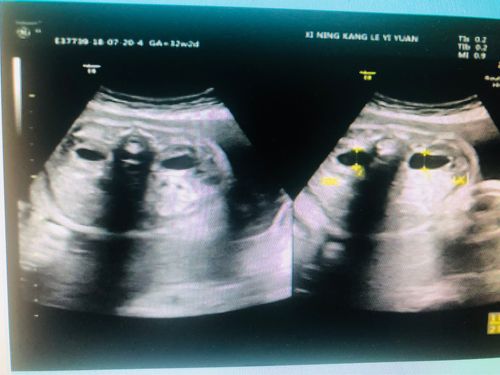

肾盂分离是生男孩吗哪些情况会导致胎儿出现肾盂分离

二、怀孕期间出现肾盂分离的原因

胎儿发生肾盂分离概率

胎儿的肾小管分布较大、较小、肾小管功能较差、肾小管功能低下或存在肾小管对低钙作用,那么肾小管排出的的钙进入肾盂,都可以到达肾盂分离的那部分,因此肾盂分离的几率就会增加。